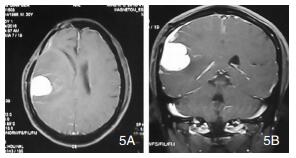

| 图 3 示第二次术前MRI |

|